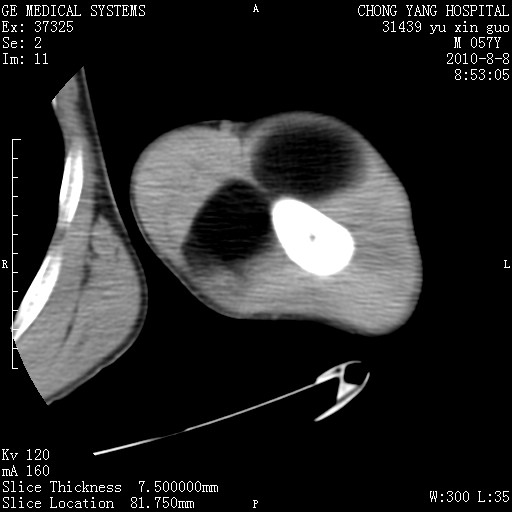

标题: CT28267:M57Y 上臂包块8年余。 [打印本页]

标题: CT28267:M57Y 上臂包块8年余。

上臂软组织内脂肪瘤。

包膜光滑、完整的脂肪密度肿块,支持脂肪瘤。